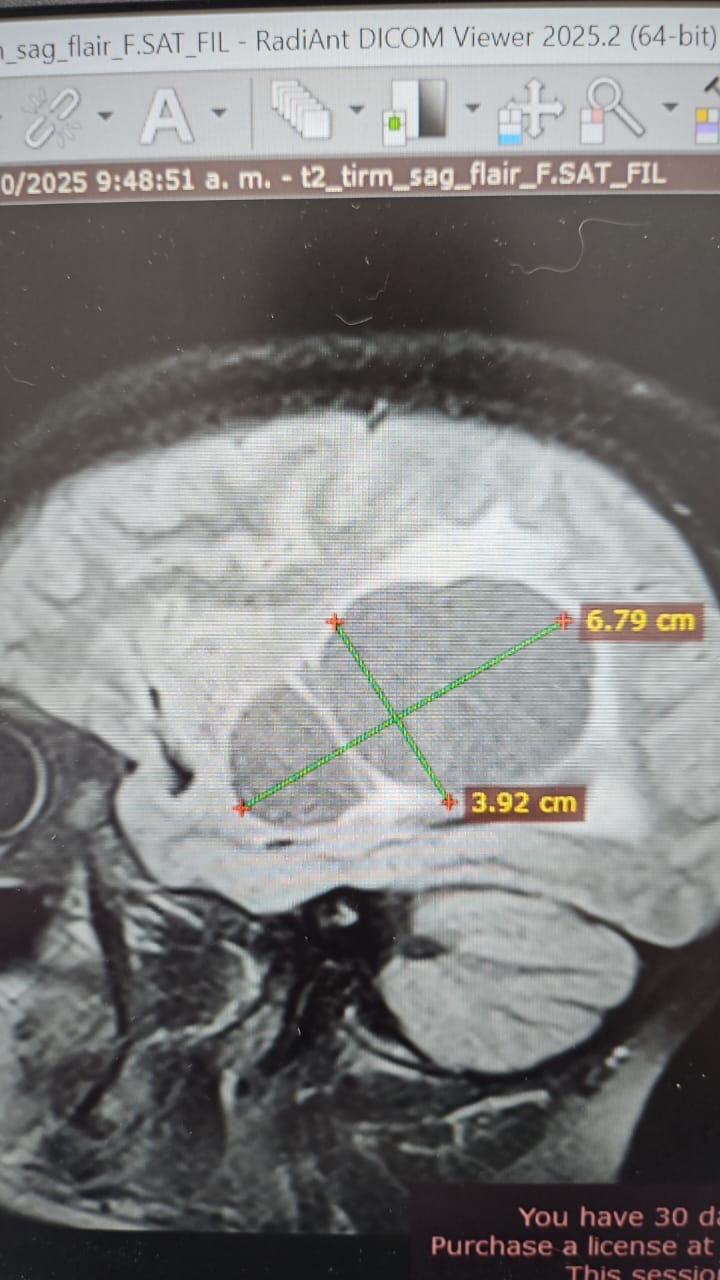

Hola, mi nombre es Yraida y estoy recaudando fondos para mi prima Ana, quien tiene varios quistes y dos tumores en el cerebro (adenoma hipofisario y craneofaringioma) y necesita una operación urgente.

Hello, my name is Yraida, and I am raising funds for my cousin Ana, who has several cysts and two brain tumors (a pituitary adenoma and a craniopharyngioma) and urgently needs surgery.